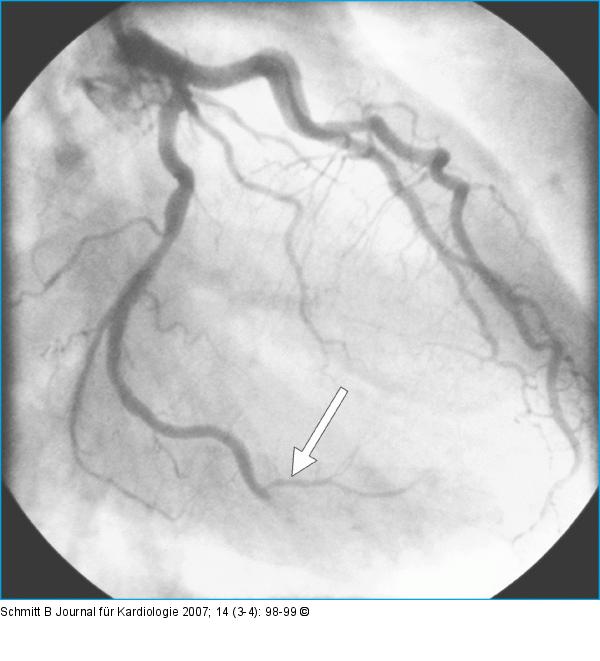

Abbildung 3: Arteria circumflexa Koronarangiographie: embolischer Verschluß des Ramus marginalis der Arteria circumflexa. |

Koronarangiographie: embolischer Verschluß des Ramus marginalis der Arteria circumflexa. |